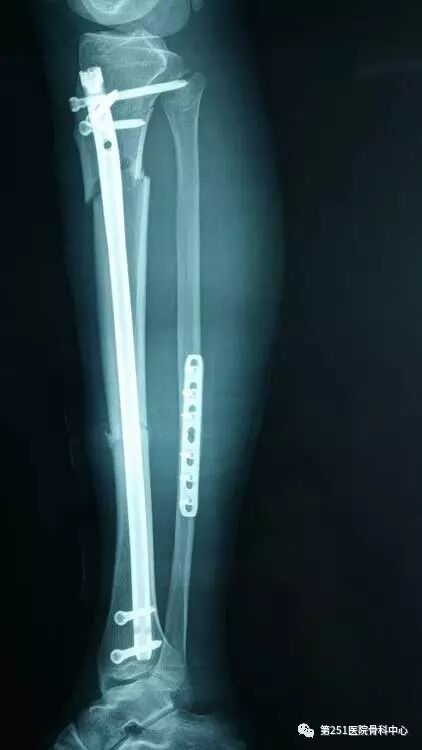

病例8:男性,24岁,车祸伤,胫腓骨近段粉碎性骨折。

![]()